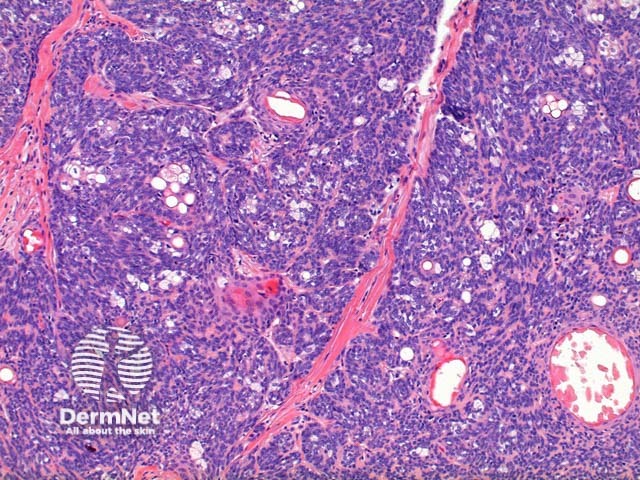

Scanning power of the histology of sebaceoma demonstrates a relatively well-circumscribed tumour nodule typically within the deep dermis frequently with attachment to the epidermis. Low power identifies a lobulated tumour, which may demonstrate areas of cyst formation (Figure 1). The tumour is comprised of basaloid cells and a minority of sebaceous cells in addition to small ducts with the crenelated eosinophilic lining seen in sebaceous ducts (Figures 2, 3 and 4). A variable number and distribution of sebocytes is seen, but should remain the minor proportion compared to the basaloid component. Frequent mitoses can be seen in this tumour, though cytological atypia is lacking (Figure 5).

Figure 2

Figure 3